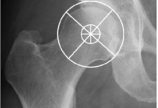

关于儿童股骨头骨骺滑脱(SCFE)的问与答。Level of Evidence:Expert opinion  学生:小儿骨科医生甲  老师:积水潭医院小儿骨科 张建立主任  学生:什么是股骨头骨骺滑脱(Slipped capital femoral epiphysis,SCFE)?和股骨颈骨折Delbet 1型(股骨头骨骺分离)是一回事吗?  老师:SCFE是在生长迅速时期的青少年,强度变低的股骨头骺板在受到由于体重过大而产生的异常应力时发生头骺相对股骨颈的相对位移。由于股骨头被固定于髋臼内,股骨头本身并未发生位移,而是股骨颈相对头骺向前向近端伴外旋。SCFE是骨病范畴,Delbet 1型股骨颈骨折是高能量导致的创伤,骺板等本身并无异常。  学生:早期如何避免漏诊?  老师:首先要想到。股骨头骨骺滑脱约75%发生于超重的青少年,大部分常见于男孩。但我科收治的患儿亦有年龄不大、身材不胖者。髋、膝负重时明显疼痛,就应想到;如伴有内旋和/或屈曲受限,就更应想到。儿童主诉膝关节不适时,需要考虑到可能源于髋关节疾患,体检时需要注意对髋关节的检查。拍片一定要拍双髋正侧位,以资对照,尤其是侧位。再有就是要熟悉X线表现,特别是在没有明显移位之前,就是骺板增宽等变化。CT平扫及冠状面重建有时有助于发现轻微移位。  学生:对SCFE病人,需常规进行内分泌系统检查吗?  老师:目前认为,甲状腺功能低下、性腺功能低下、慢性肾功能不全、接受生长激素治疗或原发性甲状旁腺机能亢进等可能导致股骨头骺板“变厚”等内分泌系统疾患是发生SCFE的危险因素。但对SCFE病人是否需行常规检查目前尚不明确,视条件而定。另外,有文献认为,如果SCFE患者合并存在内分泌系统异常,有助于是否需行预防性固定的手术决策选择。  学生:SCFE分型及其对临床治疗选择的意义?  老师:传统的,根据病程、能否负重及滑脱/移位程度对SCFE分别有不同的分型。  根据病程(Based on Onset of Symptoms):  急性:症状持续时间<3周(稳定或不稳定);  慢性:症状持续时间>3周(多为稳定);  慢性滑脱急性发作(Acute on chronic):症状持续1个月以上,轻微外伤致症状加重。  根据能否负重(Functional Classification):  稳定型:可以负重;  不稳定型:不能负重(即使拄拐亦不能)【Definition of the Unstable Slip (Loder): “Classified a slip as unstable if the child had such severe pain that walking was not possible even with crutches, regardless of the duration of the symptoms.”】  但是,需要注意的是,对于滑脱是否稳定文献存在混淆:其一是如果拄拐可以负重应该属于稳定型,不稳定型疼痛等症状类似于骨折;其二是所有的不稳定滑脱均呈现急性症状,但并非所有“急性”滑脱都是不稳定的。  根据滑脱/移位程度:按Southwick的测量方法,测量骨盆正位及蛙式位头干角的变化(与健测或正常值比较),<30°为轻度滑脱,30~60°为中度滑脱,>60°为重度滑脱。  传统观点建议治疗选择基于滑脱是否稳定,对稳定型滑脱行原位固定(in Situ Fixation),对不稳定型及早处理,行全麻下轻柔复位空心钉固定,可同期行关节减压。  Ganz等提出改良Dunn手术后,原有的分型意义受到极大的冲击。稳定的轻度滑脱可以原位固定,后期骨软骨成形解决SCFE后继发出现的FAI。其他情况均应切开复位。似乎该手术绝对安全,不会增加并发症。即便如此,术前预测AVN仍是问题。  学生:SCFE治疗的目标是什么?  老师:SCFE治疗根本目标是防止或矫正可能会导致髋关节早期的髋关节症状或步态异常及晚期的骨性关节炎的股骨头(颈)畸形。  有效的治疗干预手段应达到以下目的:  稳定头骺与股骨颈的位置关系;  减小最终的头颈畸形:早期复位;稳定骺板以避免进一步滑脱;需要时晚期截骨矫形术;  减少或避免并发症:股骨头缺血坏死(AVN)、软骨溶解、骨性关节炎等;  维持和改善关节功能。  学生:治疗时机的掌握?  老师:一旦确诊,越早越好。  学生:经过牵引以后滑脱恢复,可以不行内固定吗?  老师:固定是基本、有效治疗手段,不固定是无奈之举,病因不解除,仍有滑脱可能。  学生:牵引后部分病例可以获得“良好对位”,再行原位融合固定,远期发生FAI的风险怎么样?  老师:骨牵引可以改善髋关节活动及矫正股骨头骨骺滑移。根据股骨头骨骺滑脱的方向,可以通过骨牵引使髋关节屈曲、外展、内旋。因其作用轻缓,并发症发生率相对低。从理论上说,良好对位后远期发生FAI的风险较低。问题是如何界定良好对位?是否会出现继发改变?继发的改变是否会造成FAI?以目前的经验很难预测。  学生:对不稳定型SCFE的治疗策略?  老师:目前尚存争议。可分为两大类:  轻柔手法或改变体位的复位(positional reduction),然后空心钉固定(行/不行关节囊内血肿减压),必要时二期处理出现的畸形;切开复位:a:外科脱位入路切开复位,清除损害股骨头血供的“骨痂”等,直视下行股骨头复位(Slongo、Ganz等);b:关节囊切开血肿清除,轻柔复位后内固定(Parsch等)。  但是问题在于,这两种治疗策略孰好孰坏?术者的经验怎么样?什么才是最佳的治疗时机?  加拿大Hospital for Sick Children的Unni G. Narayanan报告了他们应用外科脱位(surgical dislocation)方法治疗真正不稳定型滑脱的早期经验,发现并发症发生率很高,与既往治疗方法比较AVN发生率没有降低。基于此,对于经验不足的年轻医生,他们的建议治疗策略:  轻柔手法或改变体位的复位,然后1~2枚空心钉固定:如果滑脱确为不稳定则可获得一定程度复位;使用牵引床内旋下肢使髌骨向上复位/改善对位,让C臂绕髋关节转;考虑血肿清除;  学习外科脱位入路的切开复位,外科脱位技术是非常有效的手术技术。但需要知道的是,SCFE的切开复位不仅仅是“外科脱位”。  学生:应用外科脱位技术对SCFE行“切开复位”,在现阶段,您认为其优势表现在哪些方面?适应症如何掌握?  老师:仅在于恢复股骨头偏心距。其他方面缺乏足够证据。据Ganz经验,病史两年以内中重度都可以做。我个人建议中重度应复位(改良Dunn手术)。但需有充分准备、训练、经验。另须有处理残留畸形或继发畸形的能力。  学生:如何最大程度降低SCFE治疗后的并发症风险?AVN是SCFE治疗时需避免的严重并发症,发生AVN的可能原因有哪些?有哪些重要的预测因素?  老师:遗憾的是滑脱的并发症与治疗的并发症相同,且治疗造成的并发症往往重于原发病的并发症,目前尚无有力证据证明治疗可以降低并发症。AVN原因可能包括滑脱本身因素与治疗相关因素。治疗可能因素包括复位手法、手术入路及截骨术式、空心螺钉位置不当等。目前认为不稳定型滑脱是发生AVN的危险因素,但是需要注意如前所述何为真正的“不稳定型滑脱”。  学生:文献报告,约15%孩子可能出现双侧受累,您会做预防性对侧的融合固定吗?  老师:除非有确凿依据,患方充分理解。国情所限,只有密切观察,待有指征。